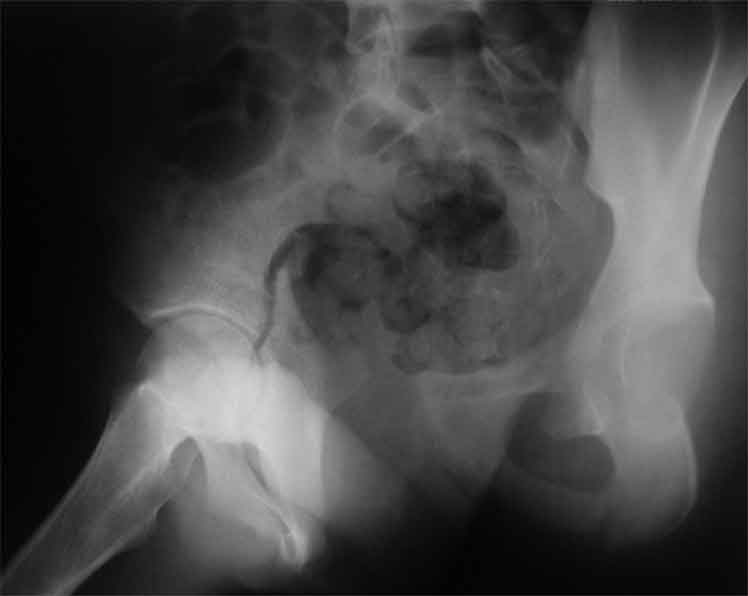

продолжение темы. не увидел энтузиазма в обсуждении. Вопросы прежние, первым этапом закрыто устранили вертикальное и передне-заднее смещение. Каким образом восстановить целостность тазового кольца, из каких доступов? Снимки в приложении